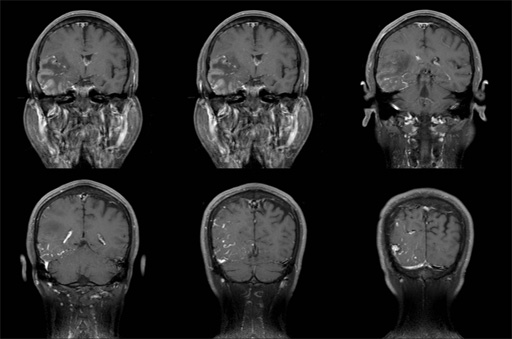

No.59症例1:50歳代、男性

1ヶ月程前より夜間に右目の奥の痛みがあり、流涙も伴う.独歩で来院.

• 図7 MRI(Gd-T1WI,Axi)

• 図8 MRI(Gd-T1WI(FS),Cor)

• 図9 MRI(Gd-T1WI,Sag)